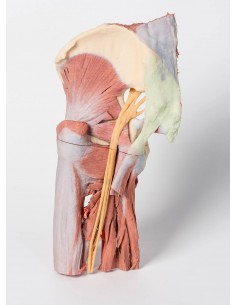

3D Anatomy 1.0 - Extremidades inferiores

Disección profunda de la fosa poplítea Erler Zimmer 3D anatomy Series MP1830